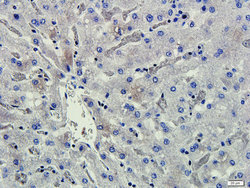

Supportive validation

- Submitted by

- antibodies-online (provider)

- Main image

- Experimental details

- IHC